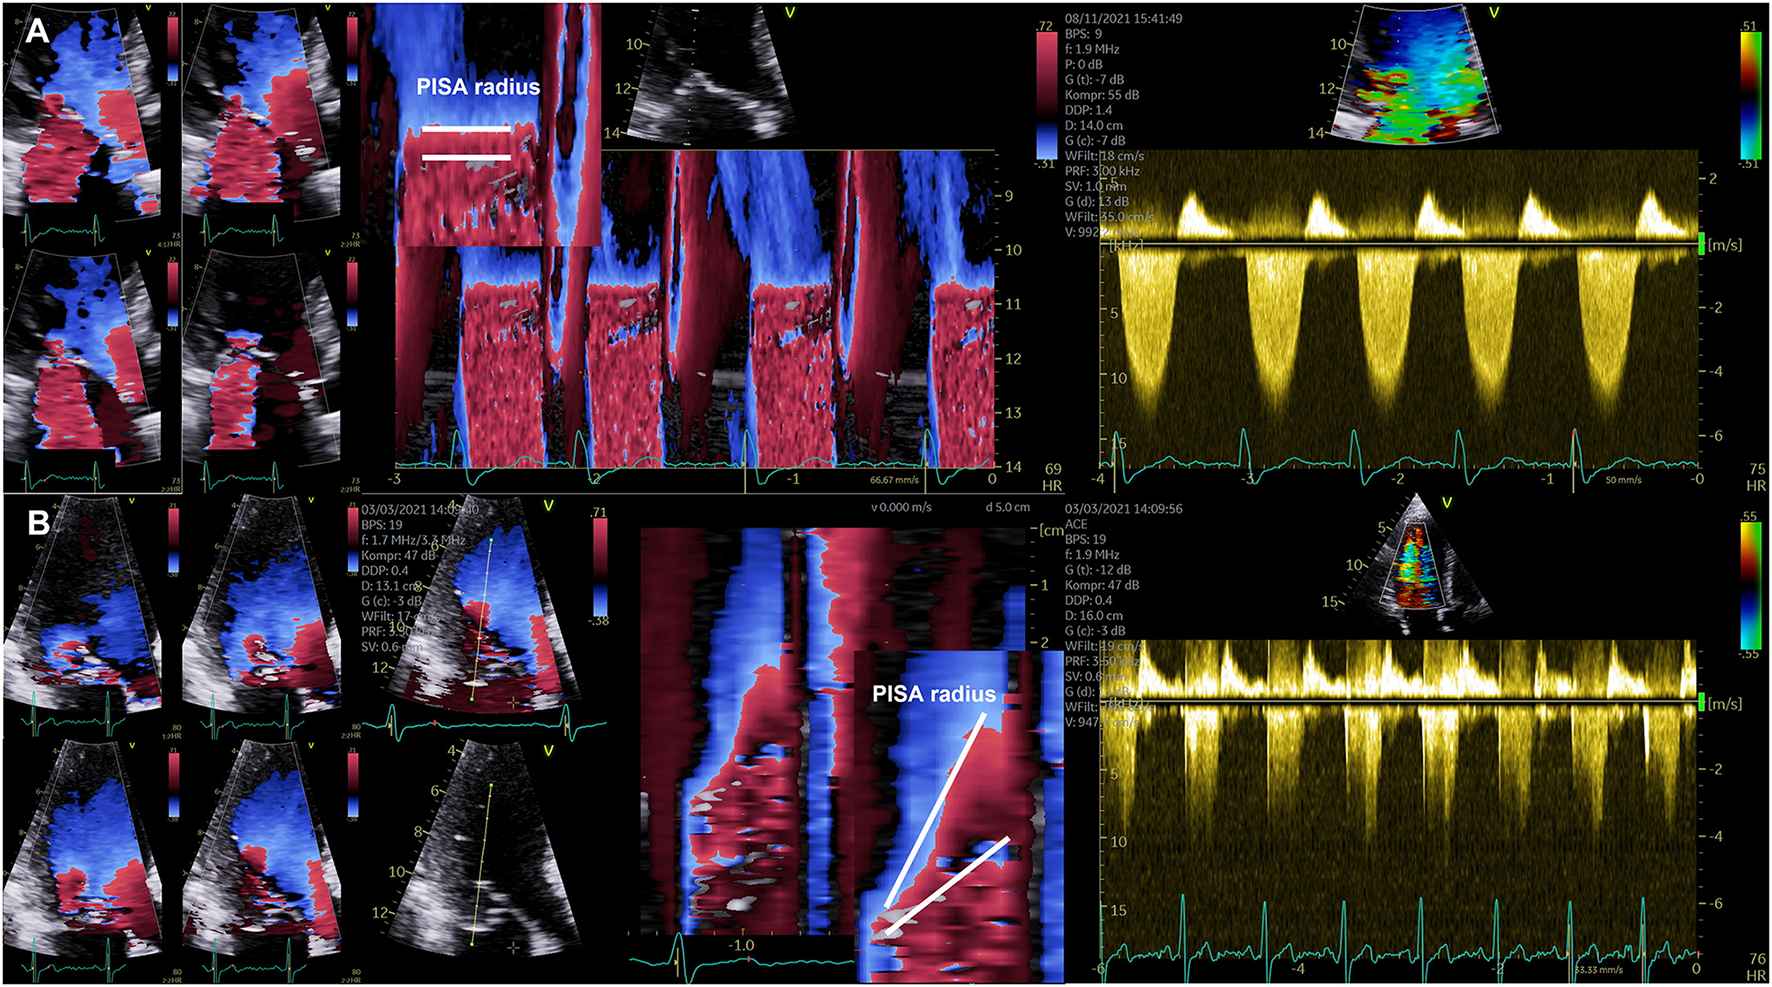

Although it is not recommended to use the jet area for MR quantification and despite of the inappropriateness to quantify MR severity by its size and its relation to the left atrium, this approach is still the most often so-called semi quantitative parameter that is used for grading of MR severity (21). The second most common method is the 2D-PISA method with its well-known limitations (21). It is obvious that dynamics of MR during systole restrict this method to a special—presumably small—subgroup of MR or FMR-patients, in whom the PISA radius is flat, and in whom the jet direction is central and perpendicular to the MA. However, such as in COAPT more than 90% of the enrolled patients were classified by the 2D-PISA method (22).

Both, EOA in AS, and EROA in MR are functional parameters, which reflect the functional EOA or EROA during systole. However, due to the dynamics of MR the EROA measured by the 2D-PISA does usually not reflect the functional EROA during systole. Due to the limitations of the 2D-PISA method the term EROA should be better labeled as EROAby 2D−PISA to avoid misunderstanding and misinterpretation (4, 6). The proper labeling of the origin of the 2D-PISA radius—entry of the orifice area vs. vena contracta—(4, 6) is one crucial point, the proper imaging of the convergence area, MR dynamics within the cardiac cycle, and ultrasound settings are additional sources of errors. In most of the cases the assessment of the EROAby 2D−PISA is the so-called maximum EROA, in which the 2D-PISA method is not applicble. An appropriate use of the 2D-PISA method can be verified by a homogenous PISA radius in the color-coded M-mode and by the ability to delineate the regurgitant velocity contour in the cw Doppler spectrum (see Figure 3).

Figure 3

Illustration of the dynamics of the PISA radius in mitral regurgitation (MR). (A) Documentation of almost stable PISA radius in a patient with secondary MR. On the left side four consecutive images during systole are shown illustrating the almost constant PISA radius. Right to these images a color-coded M-Mode illustrating the horizontal PISA radius and the continuous wave Doppler spectrum are shown. (B) Documentation of severe late systolic increase of PISA radius in a patient with primary MR. On the left side four consecutive images during systole are shown illustrating the significant increase of PISA radius at late systole. Right to these images a color-coded M-Mode illustrating the dynamics of the PISA radius and the continuous wave Doppler spectrum with the late time-to-peak regurgitant flow velocities are shown.

The CSA of the left ventricular outflow tract (LVOT) is relatively stable and transvalvular flow velocities are integrated during systole, which is why the EOA of AS can be assumed as a relatively stable value, if certain measuring errors will be avoided. In contrast—especially in eccentric MR—the velocity time integral (VTI) of regurgitant flow velocities is difficult to delineate and the PISA-radius using the 2D-PISA method varies during systole. In primary MR often a late systolic regurgitation with a late time-to-peak-shape can be observed. In FMR the PISA-radius also varies during systole in many cases. Thus, variations of both parameters cause a wide range of measuring errors often resulting in overestimation of MRRegVol and EROA with incongruences of echocardiographic measurements. The problem of assessing EROA by EROAby 2D−PISA leads to many different terms, e.g., mean or maximum EROA. EROAby 2D−PISA is also interpreted as a substitute of the mean or maximum geometric regurgitant orifice area (GROA) (22–24). The differences of GROA can be assessed and visualized by 3D-TEE indicating relevant MR dynamics in MR patients, in whom the 2D-PISA is inappropriate (see Figure 4).